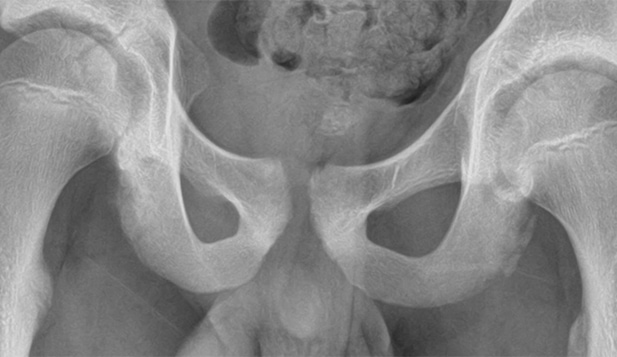

The patient is an 11-year-old boy who presents with groin pain following a soccer game yesterday afternoon.

View the image taken and consider what your diagnosis and next steps would be.

An 11-Year-Old Boy with Groin Pain After Playing Soccer